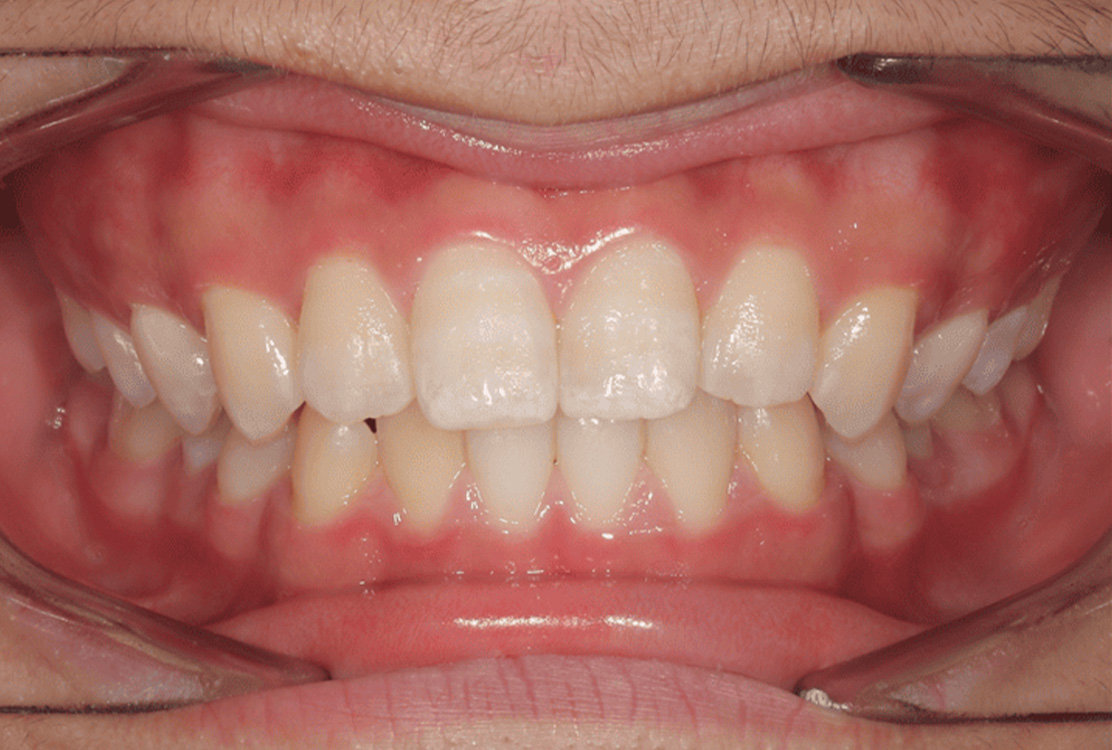

治療前